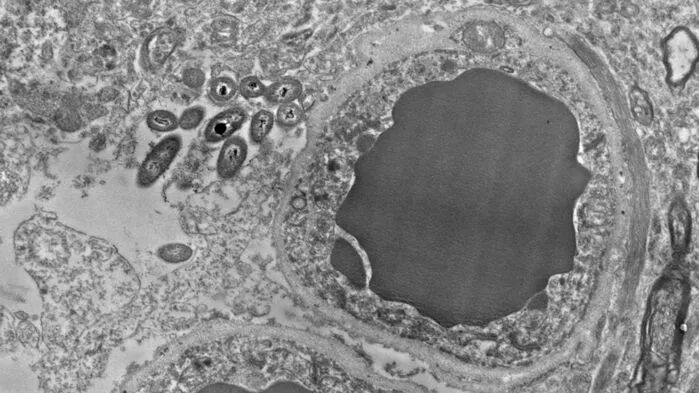

存在于大脑的一种肠道菌,AKK菌。图片来源:piscesweb

人类大脑切片里面存在细菌。图片: ROSALINDA ROBERTS

在对大脑切片显微照片的初步调查中,Robertsde 研究小组观察到脑中的细菌具有令人费解的偏好。它们倾向栖息在星形胶质细胞中,星形胶质细胞与神经元相互作用,它能够引导神经元的移动,并能维持神经元周围的离子平衡。围绕在血脑屏障血管的星形胶质细胞末端及其周围,也同样是这些微生物的聚集地。Roberts目前还无法解释这些偏好,但她考虑,这些细菌是否是被这些脑细胞中的脂肪和糖所吸引。